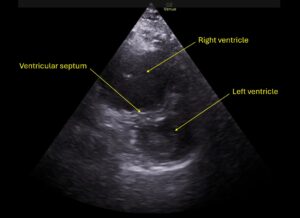

Wolff A, et al. Right atrial thrombosis. Parasternal short US 1, annotated

Wolff A et al. Right atrial thrombosis. Parasternal short US 1 annotated